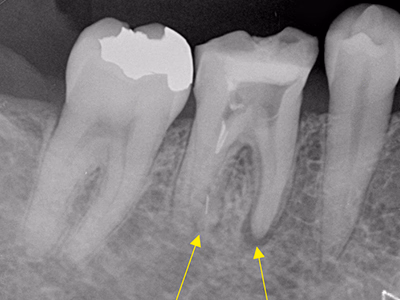

他院で抜髄処置後も咬合時違和感が続く(破折リーマー残存の情報あり)

治療内容

- ① マイクロスコープ+ラバーダム下で再根管消毒

- ② CTで破折器具の位置・長さを確認し破折リーマー除去

- ③ 症状改善を確認し根管充填

- ④ ファイバーコア築造+セラミック装着

約2ヶ月(1回の治療:1~2時間)

- マイクロエンド 132,000円

- 破折リーマー除去 33,000円

- ファイバーコア 22,000円

- 仮歯 6,600円

- セラミック冠 165,000円

慢性根尖性歯周炎の再発可能性/術後の痛み・腫脹・出血

破折器具除去と無菌的消毒を徹底し、緊密充填と精密補綴を実施。長期経過で良好。